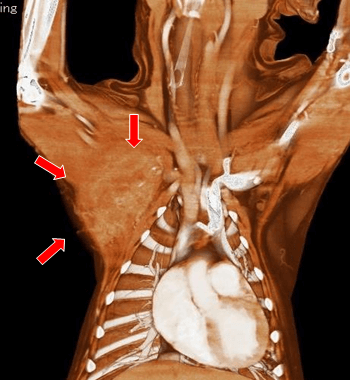

【実施症例】腋窩に発生したメラノーマに対する動注療法

ラブラドール・レトリーバー、雄、12歳。

腋窩に発生した腫瘍によって跛行を呈していた。腋窩動脈から分岐する腫瘍栄養血管に抗がん剤を注入。 実施後腫瘍の縮小が得られ跛行が改善した。

腋窩に発生した腫瘍

腫瘍栄養血管

抗がん剤の選択的注入

実施前

実施後